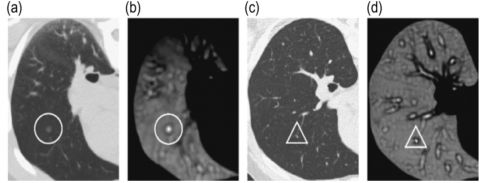

To address the urgent demand for early lung cancer diagnosis, this research concentrates on designing a system that employs advanced Convolutional Neural Network (CNN) models alongside CT imaging to detect lung nodules at an early stage. Lung nodules are often the first visible signs of lung cancer in imaging tests, and detecting them at an early stage is crucial for timely intervention [4]. CT scans [5] are commonly used in healthcare to create detailed body images, which are essential for detecting lung cancer effectively. Figure 1 illustrates the CT scan images utilized to identify the presence of a lung nodule, which is indicative of a cancerous tumor. CNNs have shown exceptional performance in image analysis tasks. Due to their capability to autonomously learn and extract meaningful features from visual data, CNNs are highly effective for medical image analysis. In this research, a range of CNN architectures will be utilized to examine CT scan images to detect lung cancer in its beginning stages. One of the primary objectives is to classify the CT images into cancerous and non-cancerous categories. The categorization of CT scan images is done with various CNN models such as VGG-19, VGG-16, MobileNet and DenseNet. Through a comparative analysis of different CNN models, the objective is to identify the architecture that offers optimal performance in classifying lung cancer from CT scans, based on indicators including precision, accuracy, and processing efficiency. Additionally, with the aim of enhancing model efficiency, an attention mechanism will be incorporated into the CNN models. The attention mechanism is incorporated to enable the model concentrating towards the most critical regions within the image—such as tumors or nodules—while minimizing the influence of non-relevant areas and overcoming the limitations of traditional CNN architectures. This mechanism helps the model to improve its feature extraction by assigning higher weights to critical areas and enabling more accurate classification.

Figure 1. The lung nodules [1]